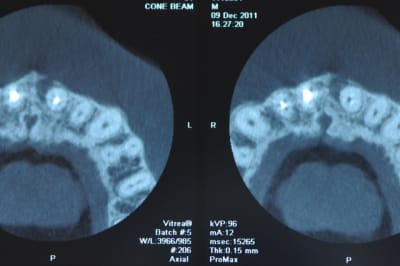

je l'envoi faire quelques coupes tomo (vivement que j'ai cone beam! )

le resultat est édifiant et sans appel; la racine est à extraire!

voili-voilà :

avant d'envoyer le patient passer son cone-beam je n'étais pas convaincu que il y avait un kyste. comme quoi!